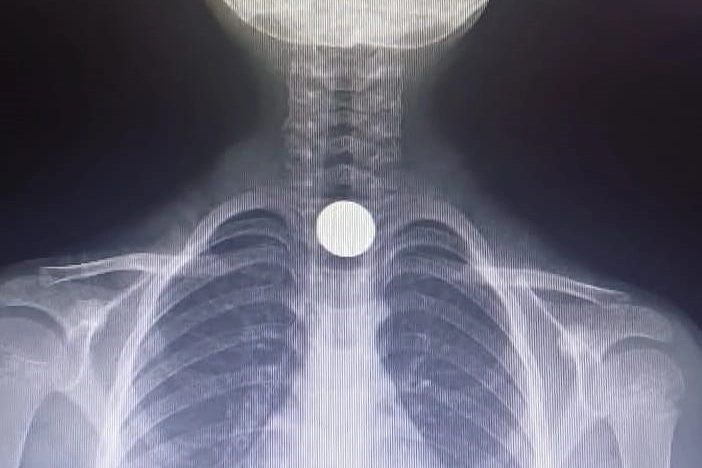

Bursa'nın İnegöl ilçesinde 5 yaşındaki çocuğun yuttuğu 50 kuruşluk madeni para yemek borusuna takıldı. Çocuk, kaldırıldığı hastanede tedavi altına alındı. Olay, Mesudiye Mahallesi Sarmaşık Sokak'taki bir apartmanda meydana geldi. Evinde oynayan 5 yaşındaki Yusuf Z., halının üzerinde bulduğu 50 kuruşluk madeni parayı ağzına götürdü. Parayı yutan Yusuf, bir anda fenalaştı. Durumu fark eden aile, çocuğu otomobille İnegöl Devlet Hastanesi'ne götürdü. Hastanede doktorlar tarafından yapılan tetkiklerde paranın yemek borusuna takıldığı tespit edildi. Çocuk, boğazındaki paranın çıkarılması için Bursa Yüksek İhtisas Eğitim ve Araştırma Hastanesi'ne sevk edildi.